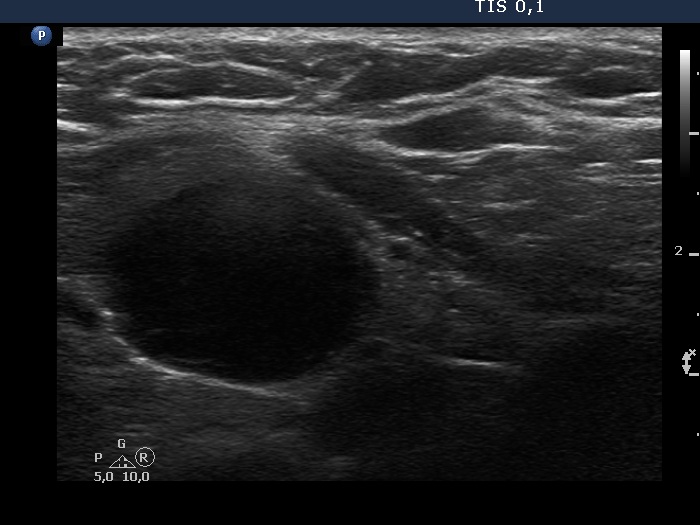

Right lobe, longitudinal scan

Lower third of the left lobe, transverse scan. Here is another very hypoechoic lesion.